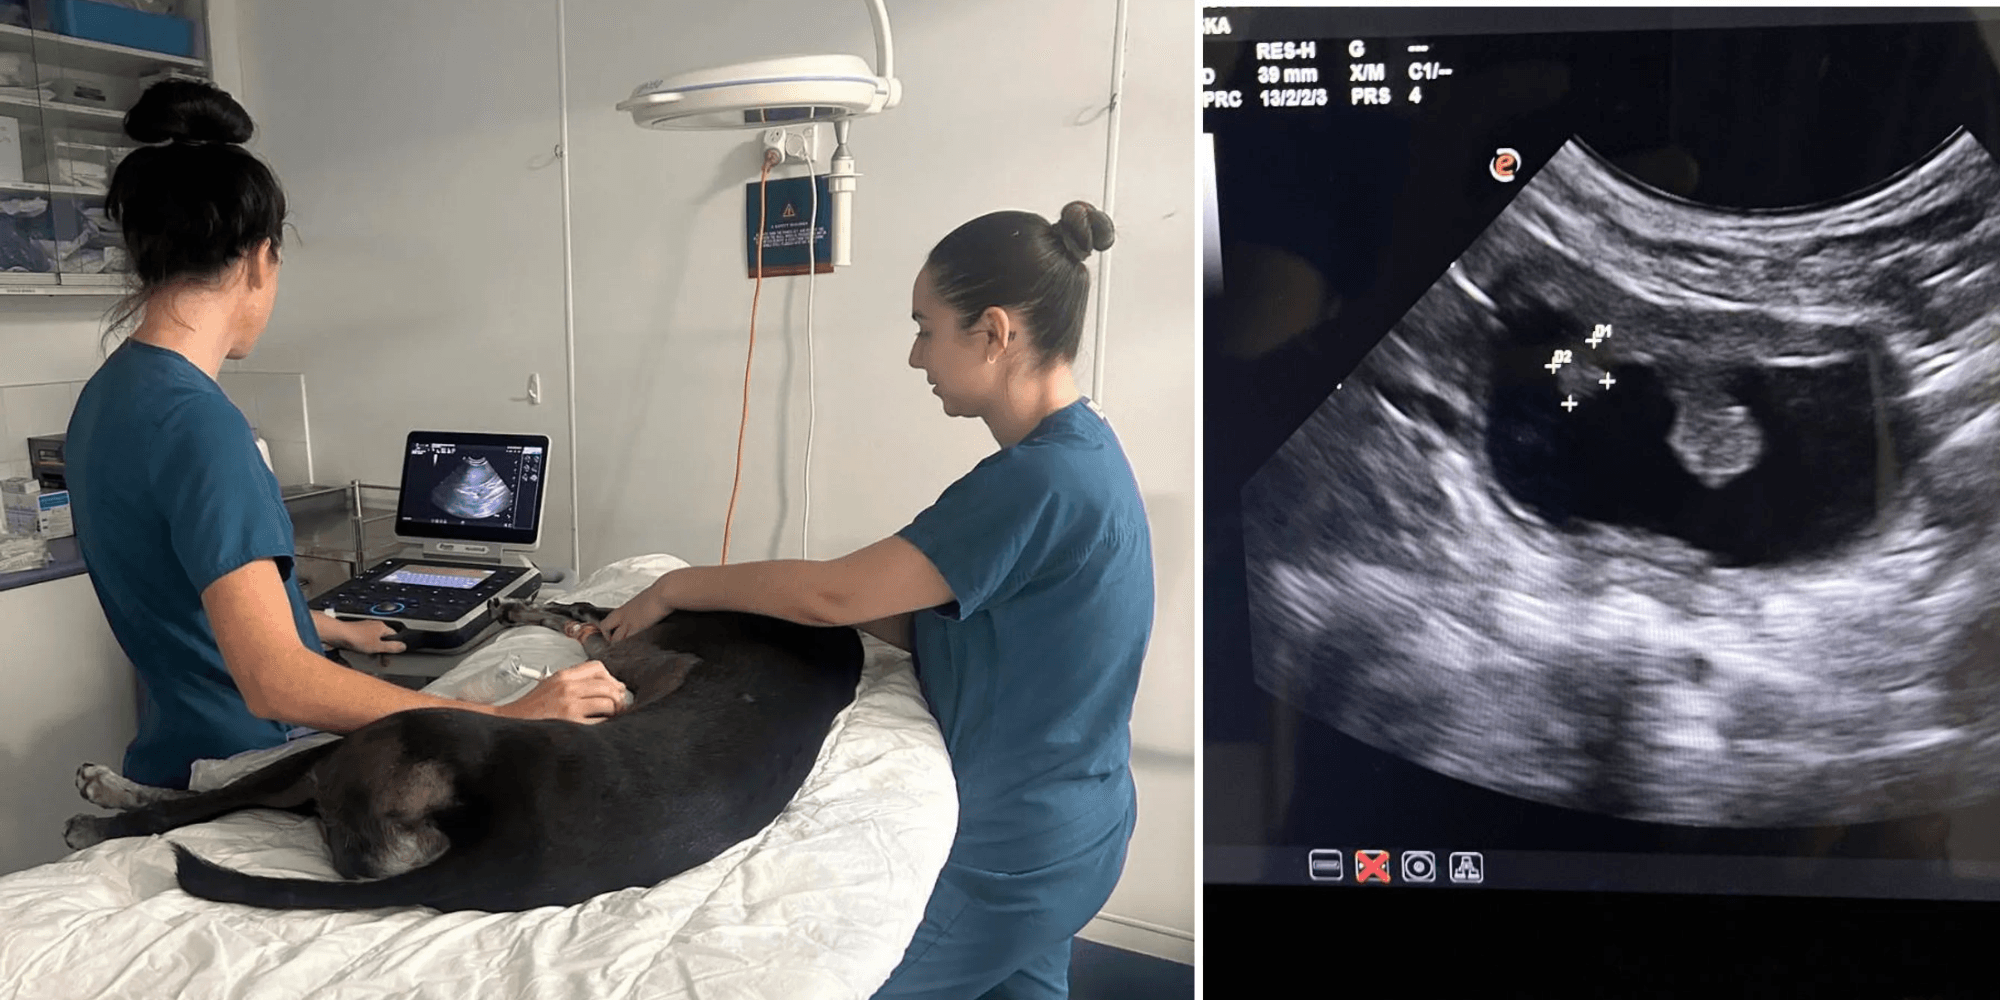

Ultrasound isn’t just for people it’s also an incredibly useful tool in veterinary medicine. While it used t...